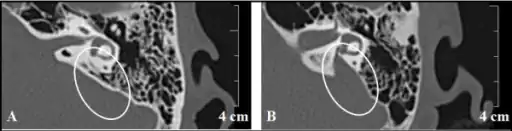

Identification of the enlarged vestibular aqueduct in a child is usually by MRI scan which identifies the fluid within the endolymphatic duct and sac. CT scan may be needed to see the vestibular aqueduct clearly. In adults CT scan may be the first investigation.